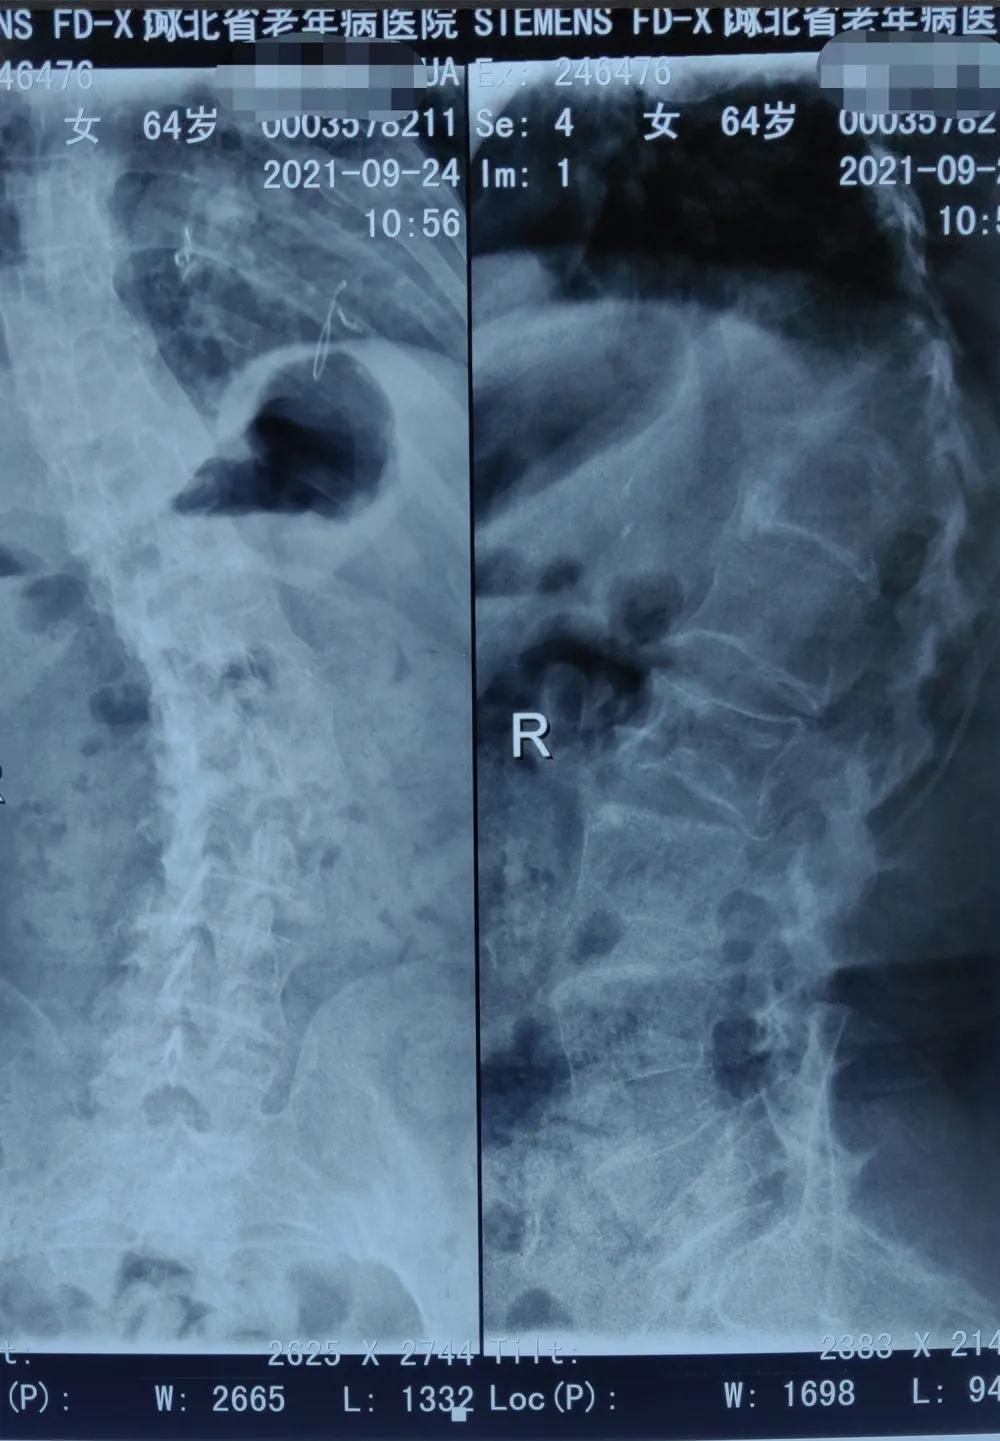

根据患者症状,张中斌查体后初步考虑为“椎体压缩性骨折”,经拍片以及做胸、腰椎核磁检查显示:脊柱侧弯,胸11、胸12、腰1、腰2椎体压缩性骨折,其中胸11椎体为新发压缩骨折,其余为陈旧性压缩骨折。

患者脊柱侧弯,增加了手术操作难度,图为张中斌术前画图寻找穿刺点

手术前

手术后